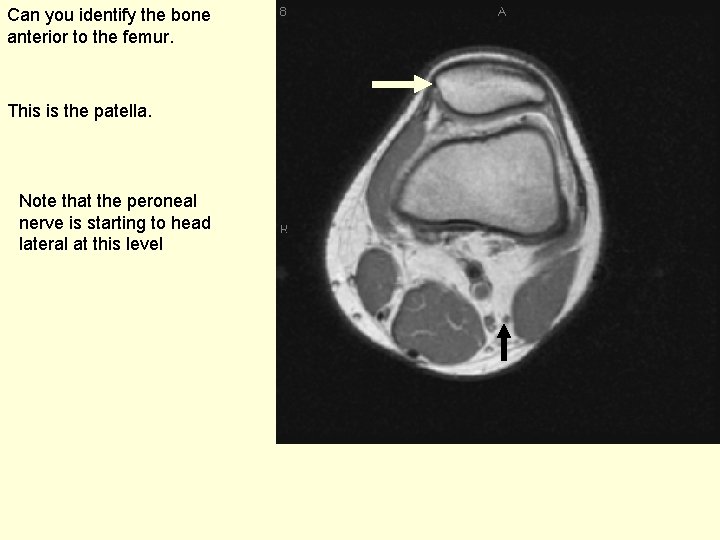

Can you identify the bone anterior to the femur. This is the patella. Note that the peroneal nerve is starting to head lateral at this level